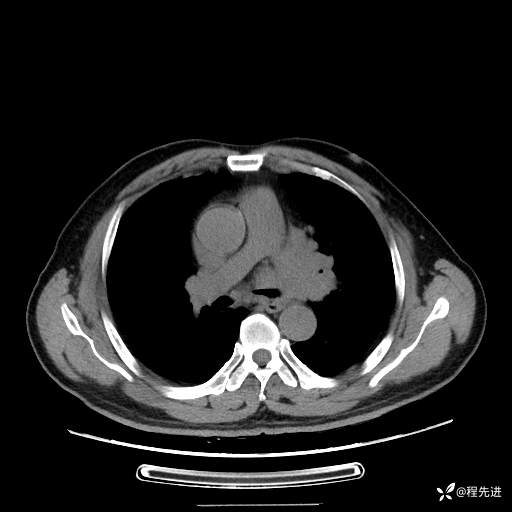

患者性别:男

患者年龄:57岁

简要病史:声嘶2月余

CT平扫+增强: